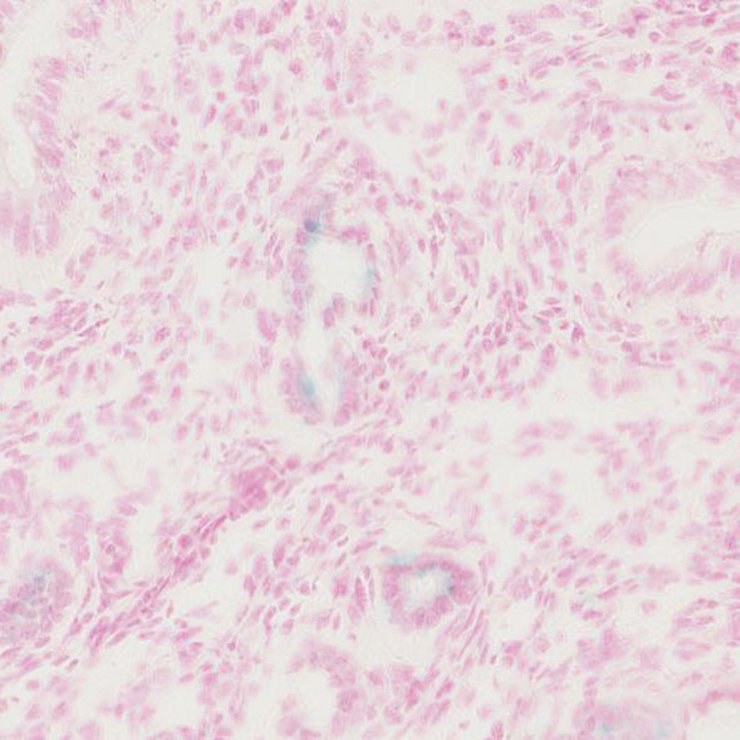

TS28: uterus Present JAX_1801932

Specimen JAX_1801936: postnatal adult; Ces4atm1.1(KOMP)Vlcg/Ces4a+ (more )

TS28: submandibular gland Present JAX_1801936

TS28: testis Present JAX_1801937

TS28: metanephros Present JAX_1801939 kidney